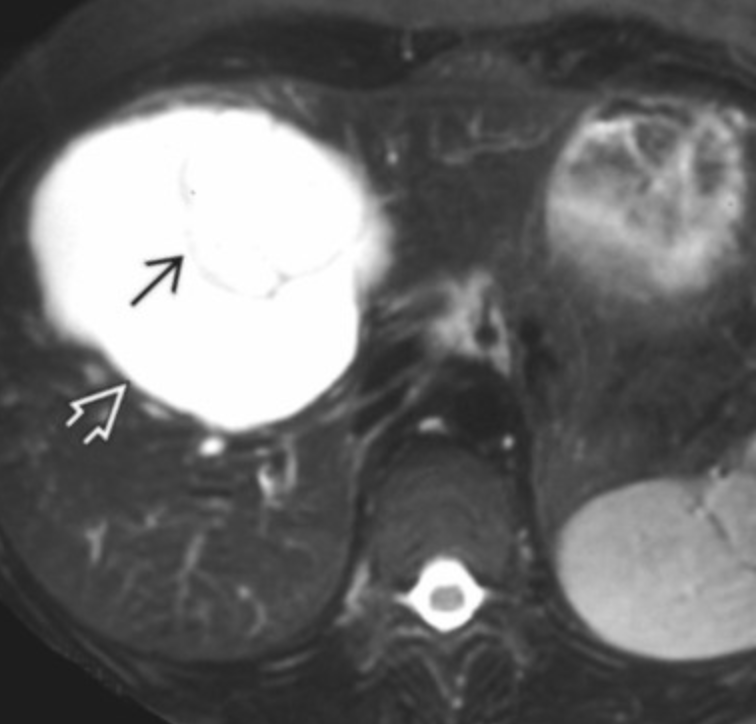

Biliary Cystadenocarcinoma

• Multiseptate liver mass

• Proteinacous fluid content better seen on MR than CT (see different signal on MR not seen on CT basically)

• Cannot really be differentiated fro biliary cystadenoma on imaging alone

• Nodularity of septa suggests malignancy